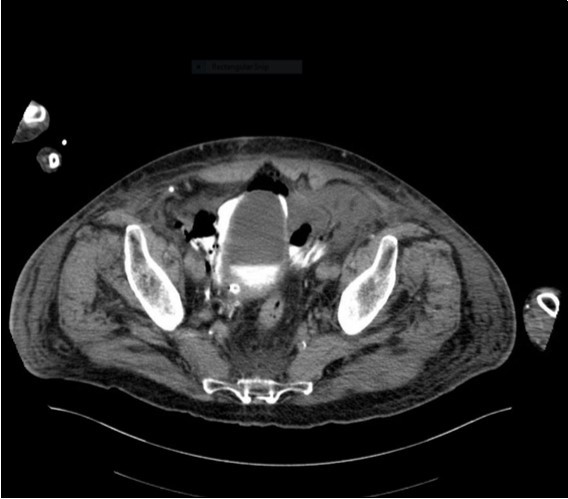

His irrigation circuit-chart showed he had received 10 litres Normal Saline via the afferent limb, but only 3 litres recorded at the efferent limb. It was suspected the catheter was adjacent to a vascular-cystic interface, however an urgent contrast CT revealed the irrigating catheter perforating the bladder, being situated in the abdominal cavity (see 3 images). His arterial blood-gas analysis demonstrated the expected normal anion-gap academia, however his Strong Ion Difference calculations, sodium-chloride difference of 13 and a normal albumin level, perfectly demonstrated the expected calculated BE of -13. The catheter was withdrawn, and the patient made a full recovery.

An urgent CT abdomen revealed a bladder perforation with the tip of the irrigating catheter situated in the abdominal cavity (Figure 1, Figure 2, Figure 3a,Figure 3b). This was most likely due to over-insertion of the 3-way catheter due to the extra force required because of the benign prostatic hypertrophy. He had therefore been receiving normal saline as ‘peritoneal dialysis’ with normal saline since insertion of the catheter. The catheter was withdrawn, and the patient made a full recovery.

Figure 3a.horizontal plane CT image 2